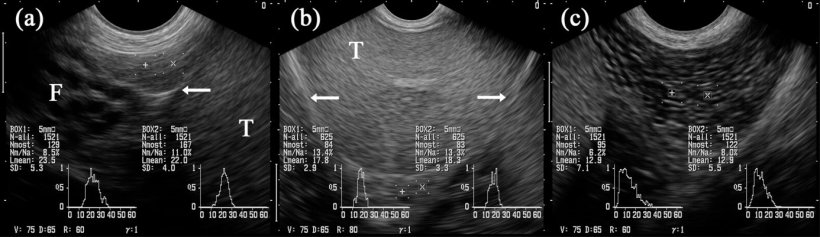

In genere, il tessuto dell'epididimo ha ugualmente una tessitura ecografica omogenea e regolare, essendo più sottile nella testa e nel corpo, e un poco marmorizzata nella coda (figura 5A-C). Tuttavia, l'ecogenicità determinata dall'"analisi di scala di grigio", è data come il valore grigio medio, differendo leggermente tra i 3 segmenti, assieme ai cambi d'immagini ottenute confrontando prima e dopo la raccolta del seme del verro (Kauffold et al. 2011).